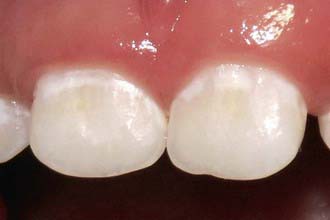

Dental caries of the primary dentition usually begins in the pits and fissures. Small lesions may be difficult to diagnose by visual inspection, but larger lesions are evident as darkened or cavitated lesions on the tooth surfaces (Fig. 304-2). Rampant dental caries in infants and toddlers, referred to as early childhood caries (ECC), is the result of a child colonized early with cariogenic bacteria and the frequent ingestion of sugar, either in the bottle or in solid foods. The carious process in this situation is initiated earlier and consequently can affect the maxillary incisors first and then progress to the molars as they erupt.

Figure 304-2 Rampant caries in a 3 yr old child. Note darkened and cavitated lesions on the fissure surfaces of mandibular molars.